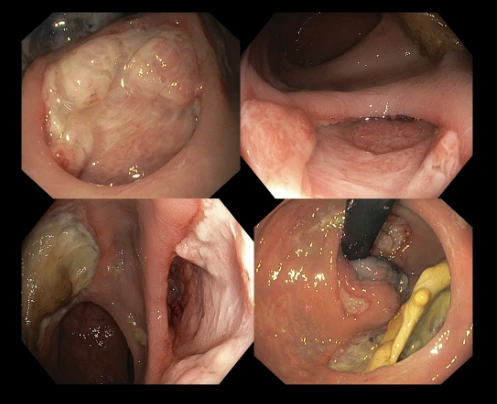

Figure 1: Fecal microbiota transplant in progress in a patient of mine – a routine colonoscopy is first performed followed by spraying of the fecal content into the patient’s small and large bowel.

Fecal microbiota transplant is an expensive procedure and is not covered by medical benefits or insurance, and our patient is not keen to undergo such tests where there is no full guarantee on a positive outcome. We do however have other patients who experienced favourable prognosis and have been doing well without laxatives.